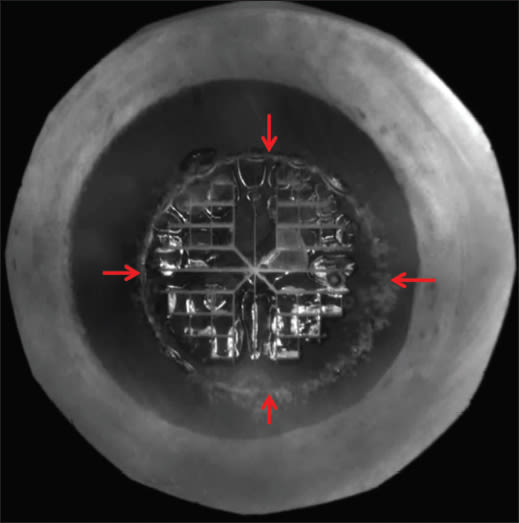

Perfectly sized (5.0 mm) and positioned, round anterior capsulotomy (red arrows) with four- quadrant segmentation and softening (0.5 mm cubes) created by a femtosecond laser.

Catalys is designed to perform four incisions: capsulotomy, lens fragmentation, relaxing incisions and cataract incisions. Results of the clinical study, which compared 29 laser-treated eyes with 30 manually-treated eyes, showed great improvement across the following steps.

► A 12-fold improvement in precision of sizing the capsulotomy with Catalys as compared to the manual technique, and a five-fold improvement in the precision of the capsulotomy shape. These findings are deemed significant, as capsulotomy shape and size are known to have a critical impact on refractive outcomes.